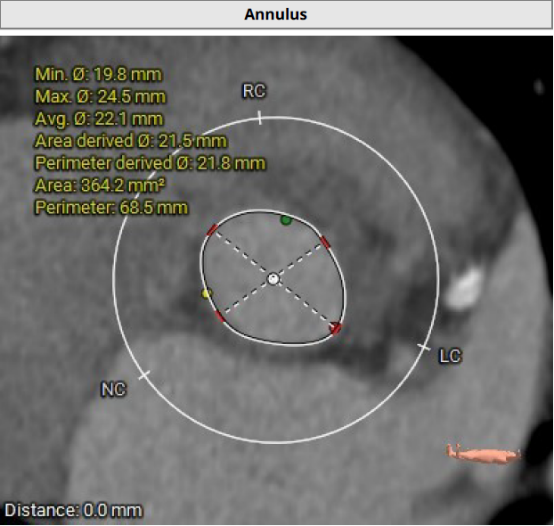

术前影像学评估

主动脉瓣瓣环及其他基本平面测量

主动脉瓣瓣上及瓣下多平面测量

超声心动图提示:三叶式主动脉瓣,瓣叶钙化合并重度狭窄及轻度反流;二尖瓣轻关闭不全;左房增大,左室壁增厚。主动脉瓣口收缩期Vmax=4.7m/s;PGmean=48mmHg;EOA=0.71cm²。